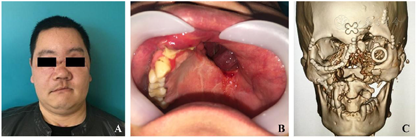

入院时检查:体温36.8℃,心率111次/分,呼吸21次/分,血压126/72 mmHg(1 mmHg=0.133 kPa),意识清楚,端坐呼吸。颌面部不对称,左眼无光感。自右侧面部外眦下3cm处至左侧颊部耳前5 cm处可见一长约15 cm伤口,与口腔鼻腔贯通。右侧眼睑下缘可见一长约3 cm的伤口,左侧外眦至眉弓外缘有一长约2 cm伤口。面部肿胀明显,左侧面部较右侧塌陷,右侧上颌骨、双侧颧骨、额骨及副鼻窦压痛明显。双侧颞下颌关节动度一致,无压痛、弹响。张口正常,张口型无偏斜。口腔鼻腔内充满暗红色血痂,12-27牙缺失、32-45牙缺失,上下颌多处牙龈撕裂,咬合关系紊乱。舌尖缺如,舌背与舌腹分离,左侧口底牙槽嵴下缘可见一长约4 cm伤口,左侧舌下腺暴露(图1)。

受伤当日排除手术禁忌后急诊全麻下行气管切开术、颌面部多发性骨折切开复位内固定术、左眼外伤探查术、颌面部外伤清创缝合术,由于患者已经出现呼吸道梗阻表现,且口腔内伤情复杂,为保证安全,我们首先进行气管切开,术中探查颌面部软组织外伤、左眼外伤及颌骨骨折情况,尽量按照解剖结构复位骨折断端,摘除左眼眼球,依次缝合面部及口内伤口(图2,图3)。术后根据患者病情送入ICU继续治疗,待病情平稳后转回我科继续治疗,正常出院。